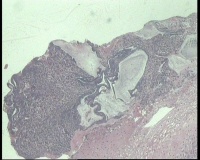

镜下见鳞状上皮大部分如(图1) ,仅局灶鳞状上皮异型(图2-4),细胞似牵拉变形,部分腺腔内见异型细胞团,这些细胞跟LEEP刀手术电凝有关系吗?这个怎么报?累腺明显,上皮图1怎么报?能报CINII—III累及腺体吗?还是宫颈高级别鳞状上皮内病变累及腺体

图3